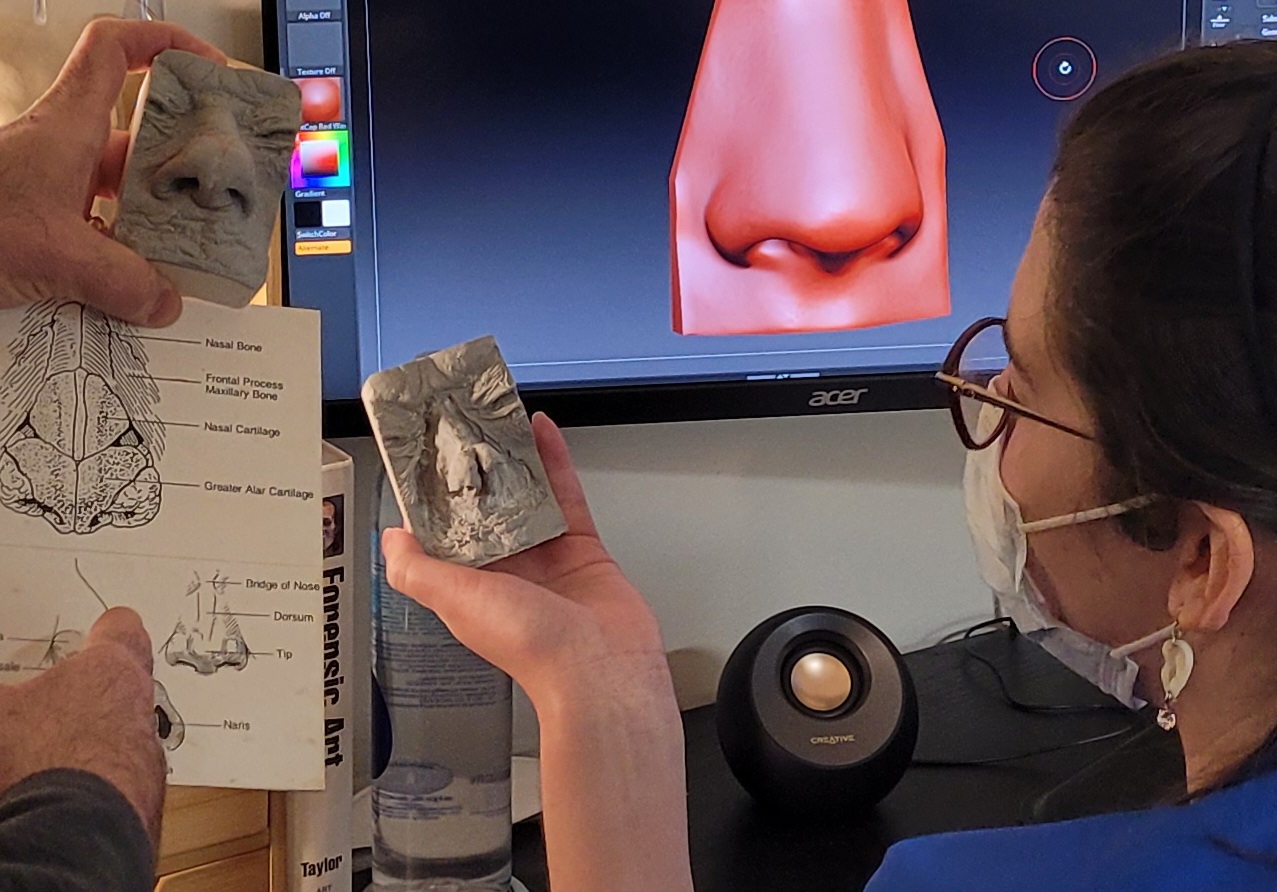

Andrew comes to Hopkins with 10-years of experience in the field of clinical anaplastology, creating custom facial and somatic prosthetics. His services provide treatment options to patients for whom surgical reconstruction alone cannot restore facial features or the appearance of limbs and digits. His custom prosthetic devices allow patients to resume activities of daily living.

Andrew has collaborated with orthopedic and hand surgeons from Duke University and faculty in the School of Dentistry at University of North Carolina at Chapel Hill in challenging reconstructive cases. He creates craniofacial devices including prostheses for large facial defects, custom cranioplasty implants, surgical guides/models, mandible prostheses, and graduated ocular conformers for pediatric patients. Andrew is one of few practitioners worldwide holding certifications in anaplastology as well as mastectomy fitting, pedorthics, orthotic fitting, and ocularistry.

- IAA Workshops, Intro to ZBrush, Digital Sculpting in ZBrush, Data Import and Export in ZBrush (DICOM and 3D Scanning), Intro to Scanning and Digital Design with Geomagic Touch Haptic Technology, Intro to 3D Printing/Additive Manufacturing Technology (Stereolithography and ColorJet Printing), UC Denver Digital Animation Lab and 3D Systems, Denver, CO, 2014

- ZBrush for the Anaplastologist Basic and Advanced, Augusta University, Augusta GA, 2016

Ear and Eye Prostheses

Patient maxillofacial prosthetics in silicone

Adhesive and Anatomically Retained Prosthetics

Principles of Clinical Anaplastology Practice

3D Technologies

Somatic Prosthetics

Osseointegrated Implant-Retained Facial Prosthetics